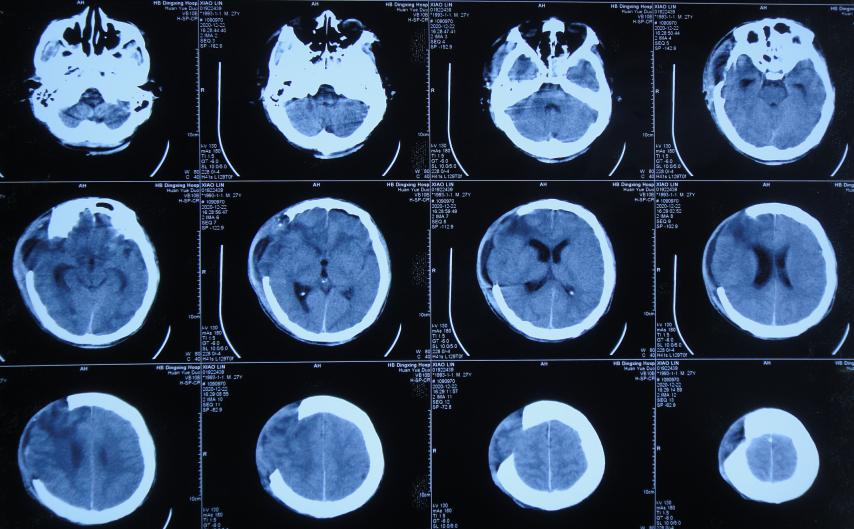

开颅术后13天即2020年12月25日(拔除腰大池引流管5天后),查头颅CT示脑膨出严重,脑积水( 图-7 )。

图-7: 2020年12月25日头颅CT

脑脊液培养提示为鲍曼不动杆菌,于2020年12月26日,查头颅CT( 图-8 )后,进行了脑室外引流术,引流出脑脊液内有大量脓液;因颅内感染严重该院医生建议患者家属转至北京北亚骨科医院的李小勇脑脊液科进一步治疗。

图-8: 2020年12月26日头颅CT